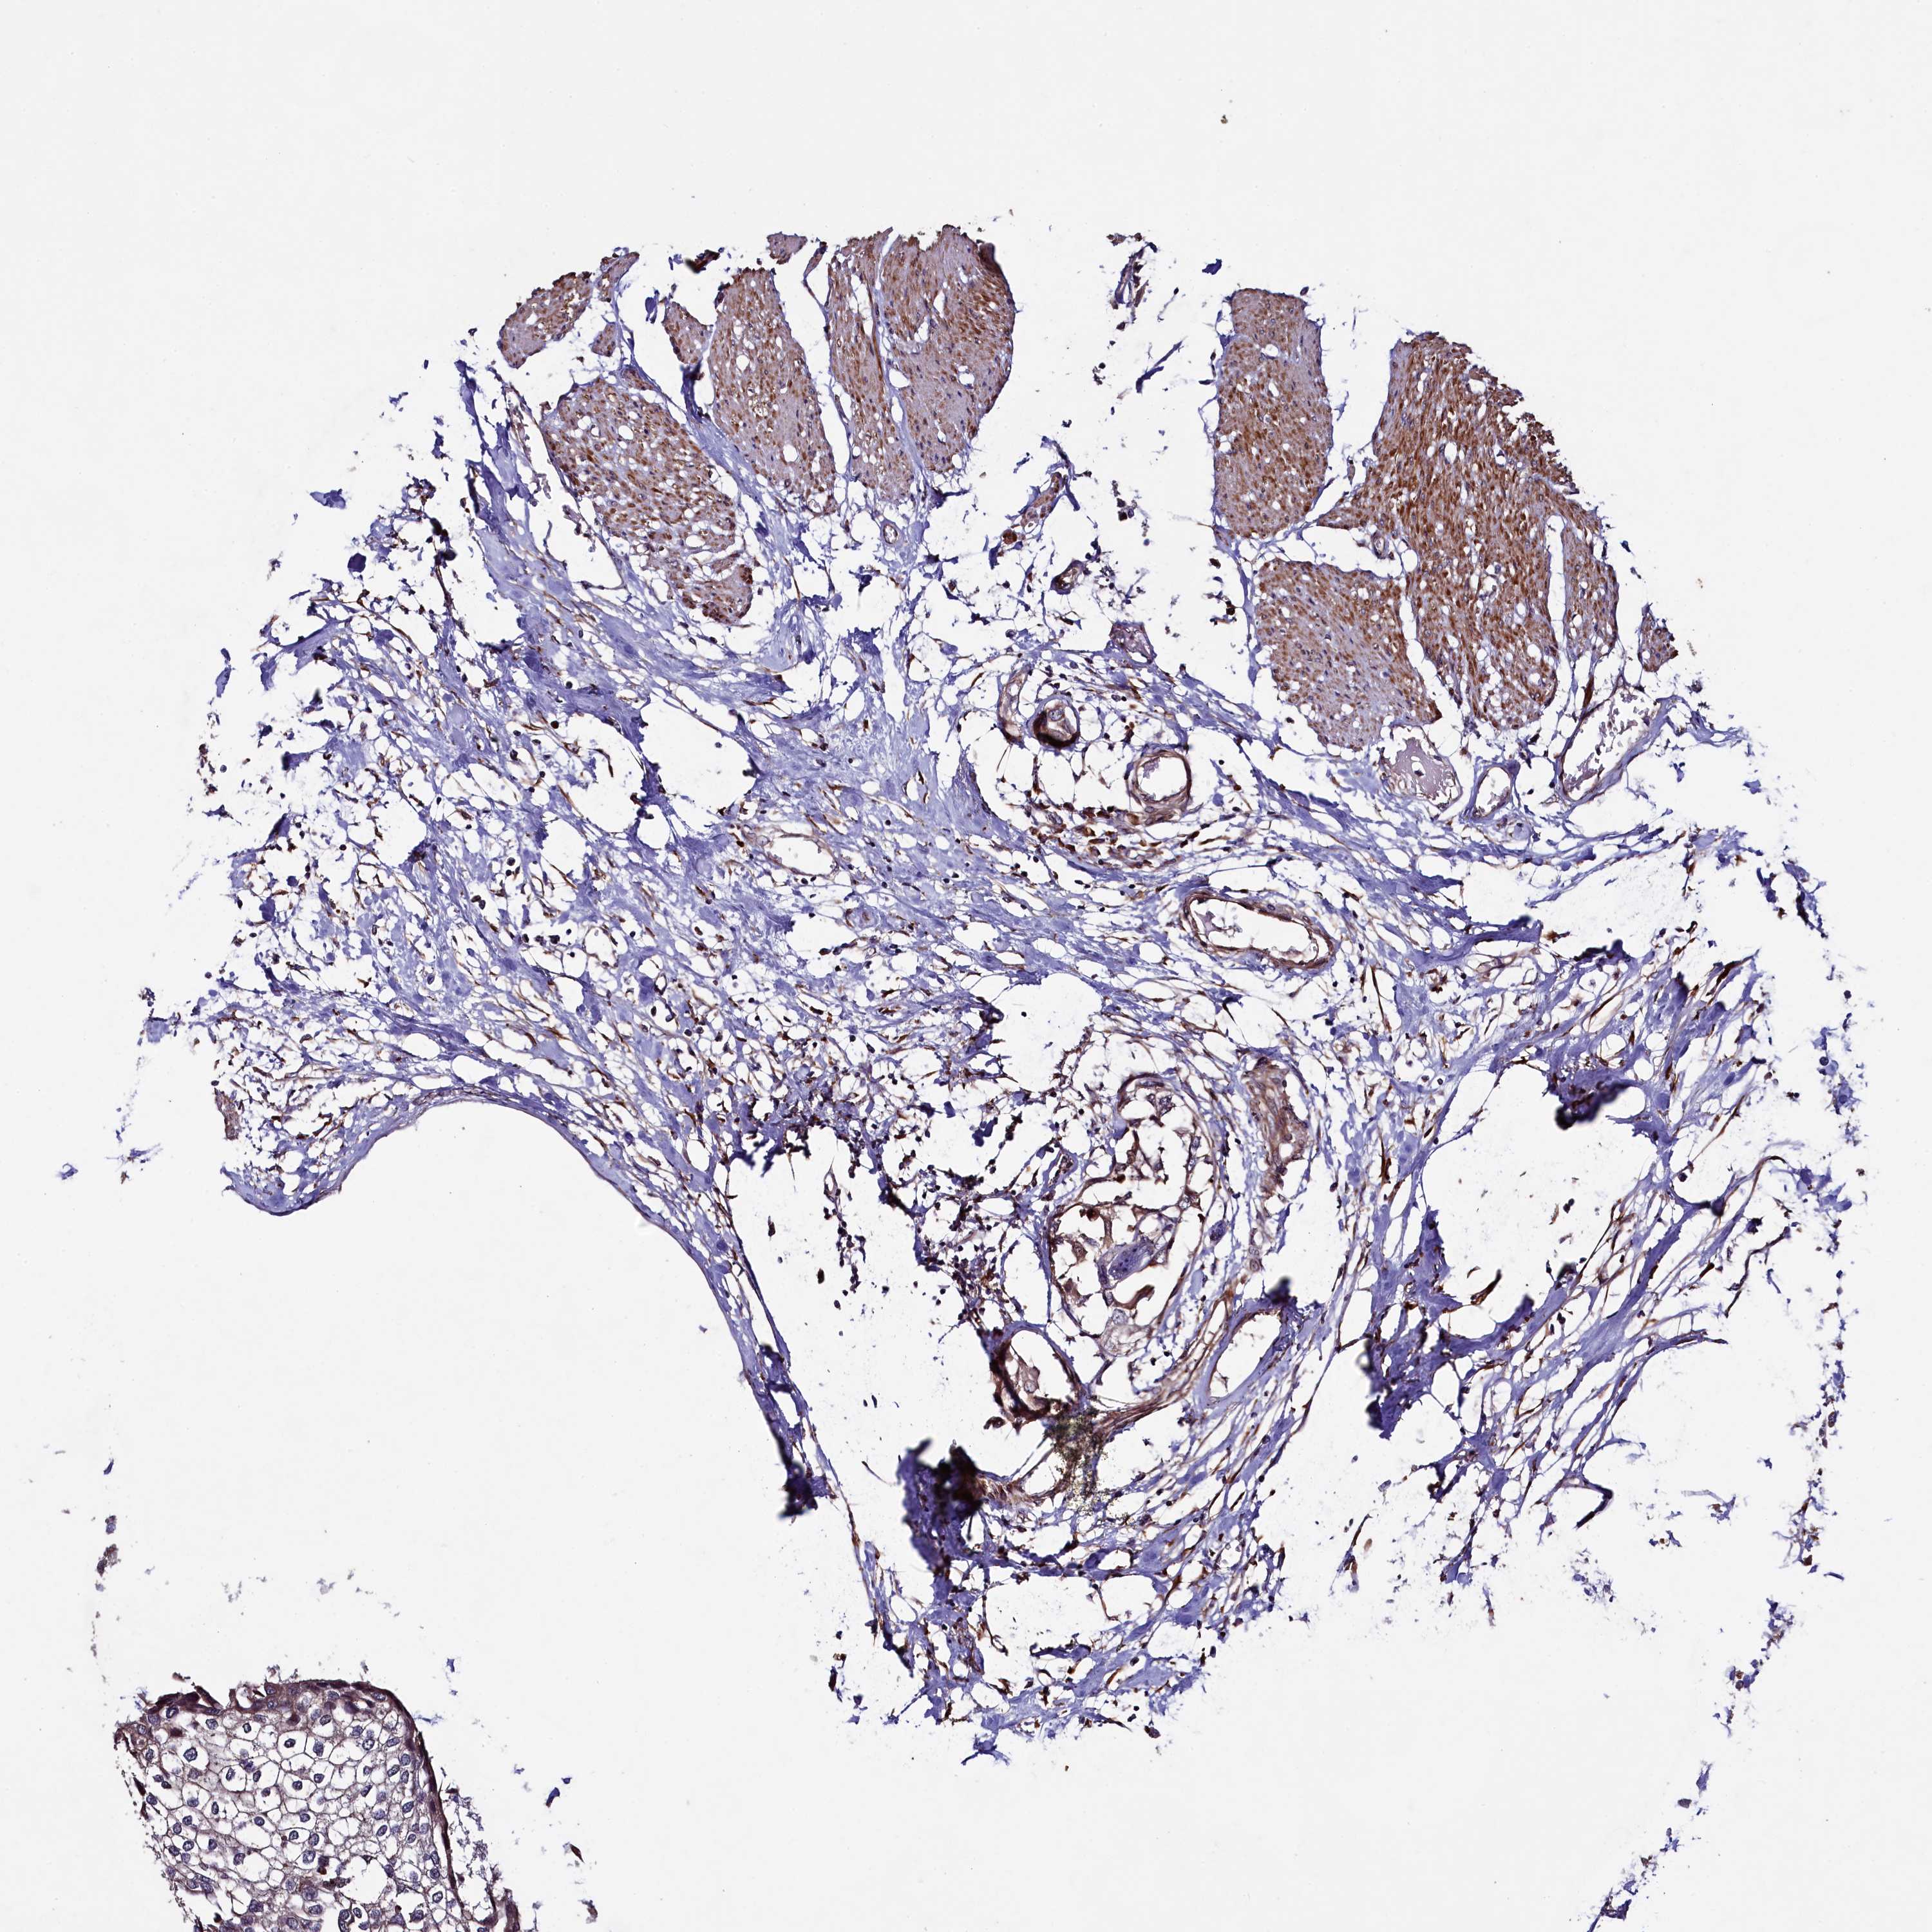

UROTHELIAL CANCER - Protein expressioni

A mouse-over function shows sample information and annotation data. Click on an image to view it in a full screen mode. Samples can be filtered based on level of antibody staining by selecting one or several of the following categories: high, medium, low and not detected. The assay and annotation is described here.

Note that samples used for immunohistochemistry by the Human Protein Atlas do not correspond to samples in the TCGA dataset.

Antibody stainingi

Antibody staining in the annotated cell types in the current human tissue is reported as not detected, low, medium, or high, based on conventional immunohistochemistry profiling in selected tissues. This score is based on the combination of the staining intensity and fraction of stained cells.

Each image is clickable and will lead to virtual microscopy that enables deeper exploration of all samples and also displays staining intensity scores, fraction scores and subcellular localization as well as patient and tissue information for each sample.

Antibody HPA040598

Antibody HPA040958

Urothelial carcinoma, High grade

Urothelial carcinoma, Low grade